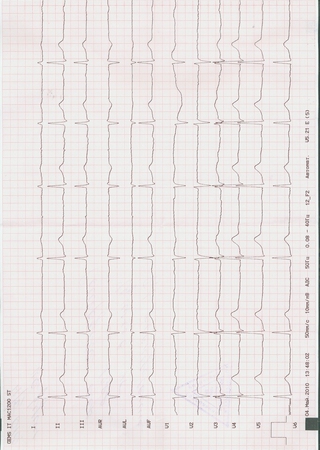

4) ЭКГ